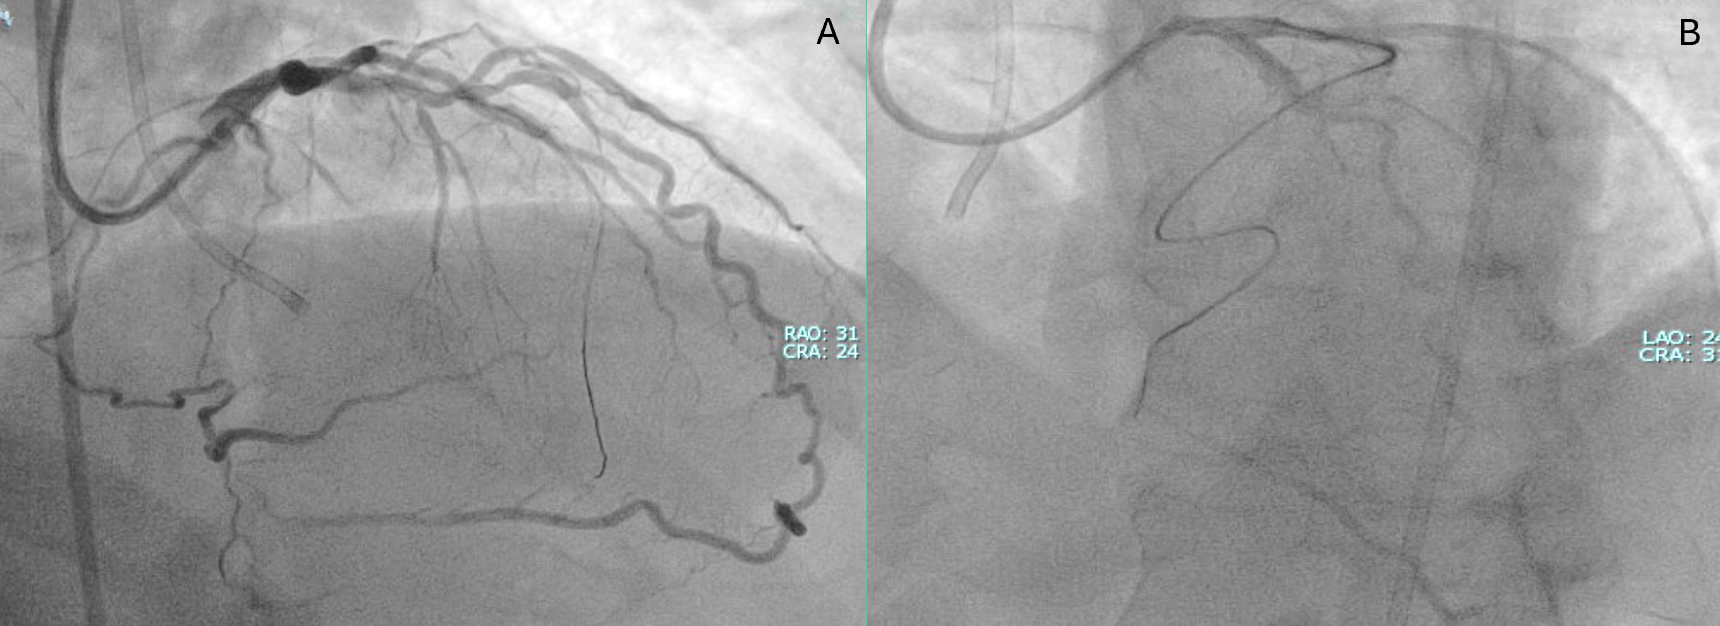

A primary retrograde strategy was selected but septal collateral wiring was unsuccessful. Epicardial collaterals from the LAD were subsequently crossed (Figure 2, Video 2); however, a retrograde wire (Confianza Pro 12; ASAHI INTECC) failed to puncture the distal cap. Antegrade wire (Gladius MG; ASAHI INTEC) knuckle was used until just before it reached the distal cap (Figure 3, Videos 3 and 4). A 3.0 x 20-mm TREK balloon (Abbott) was delivered retrogradely through the epicardial collateral and inflated at the bifurcation (Video 5). Next, an antegrade wire (Gladius EX; ASAHI INTECC) was delivered into the distal true lumen of the posterior descending artery (Figure 4, Video 6). The RCA was successfully stented with an XIENCE Pro drug-eluting stent (Abbott), with restoration of Thrombolysis in Myocardial Infarction 3 flow (Figure 5, Video 7).